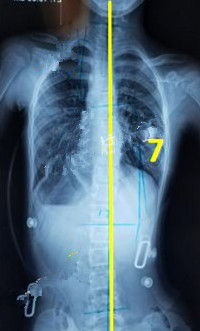

脊柱側(cè)彎矯形器(支具)是通過外力對側(cè)彎的脊柱進行矯正。所以,支具的力點位置及大小非常重要。當(dāng)患者生長發(fā)育速度較快或支具矯正效果較好時,側(cè)彎矯正的進程也會較快,此時為了充分利用孩子生長階段的最佳矯正期,一定要對支具進行及時的調(diào)整和更換。

一般經(jīng)過三個月至六個月的治療,對稱度都能得到改善,力線回正。

此時由于患者已經(jīng)完全適應(yīng)支具的力點,且體表變化較大,為了進一步矯正,我們需要對支具進行調(diào)整。如果由于孩子身高的變化較大,為了更進一步的矯正,可以考慮更換新的支具。

穿支具后